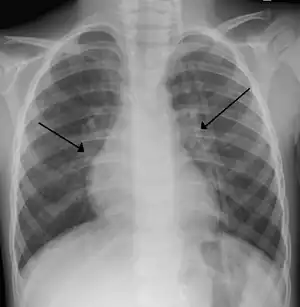

Imaging findings

Chest x-rays findings in children with RSV bronchiolitis are generally nonspecific and include perihilar markings, patchy hyperinflation, and atelectasis.[16] However, the American Academy of Pediatrics (AAP) does not recommend routine imaging for children with presumed RSV bronchiolitis because it does not change clinical outcomes and is associated with increased antibiotic use.[16][35] Chest x-ray is sometimes considered when the diagnosis of bronchiolitis is unclear or when there is an unexpected worsening.[35] In adults with RSV infection, chest films are often normal or demonstrate nonspecific changes consistent with viral pneumonia, such as patchy bilateral infiltrates.[38]